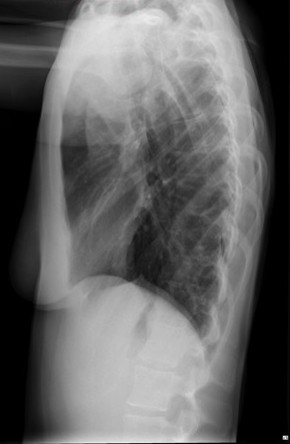

CASO: Febrícula y tos de 4 días de evolución.

Hallazgos:

- En la placa PA se observa una asimetría en los hilios pulmonares, el hilio izquierdo tiene una densidad aumentada.

- Tras examinar la placa lateral se observa un aumento de densidad en la columna que puede ser compatible con una condensación, es el signo de la desnificación vertebral.

SIGNO DE LA DENSIFICACIÓN VERTEBRAL: En la radiografía lateral normal, la densidad de la columna torácica tiende a disminuir desde la parte superior hasta el diafragma; la alteración de ese patrón por la presencia de una densidad superpuesta a la columna, indica la existencia de una consolidación pulmonar. Este signo adquiere especial valor cuando en la proyección posteroanterior la consolidación está oculta en el espacio retrocardíaco o en la base pulmonar.